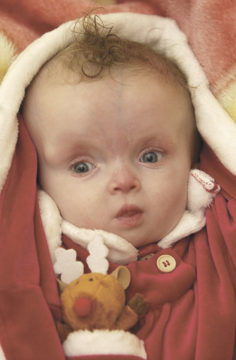

МРТ снимки мальформации Денди-Уокера